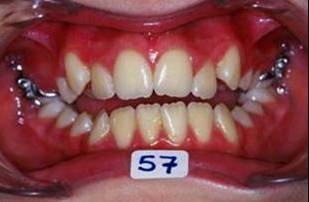

Suite de cas:

J'ai oublie de signaler que depuis RDV 4 une reeducation linguale, au cabinet faite par moi-meme, a commence.

Collage bas fait presque 3 mois apres le haut, avec des elastiques verticaux pendant 3 semaines seulement. Et voici les photos, la suite je vous en passe car il s'agit de simple finition.

Les ponits forts dans cette reeducation sont: maitriser la respiration, reformer le maxillaire, une cooperation extra et une simplicite du system utilise. Merci pour votre attention et a la prochaine... Bonne annee 2007 a tous

P.S. photos au moment du collage bas